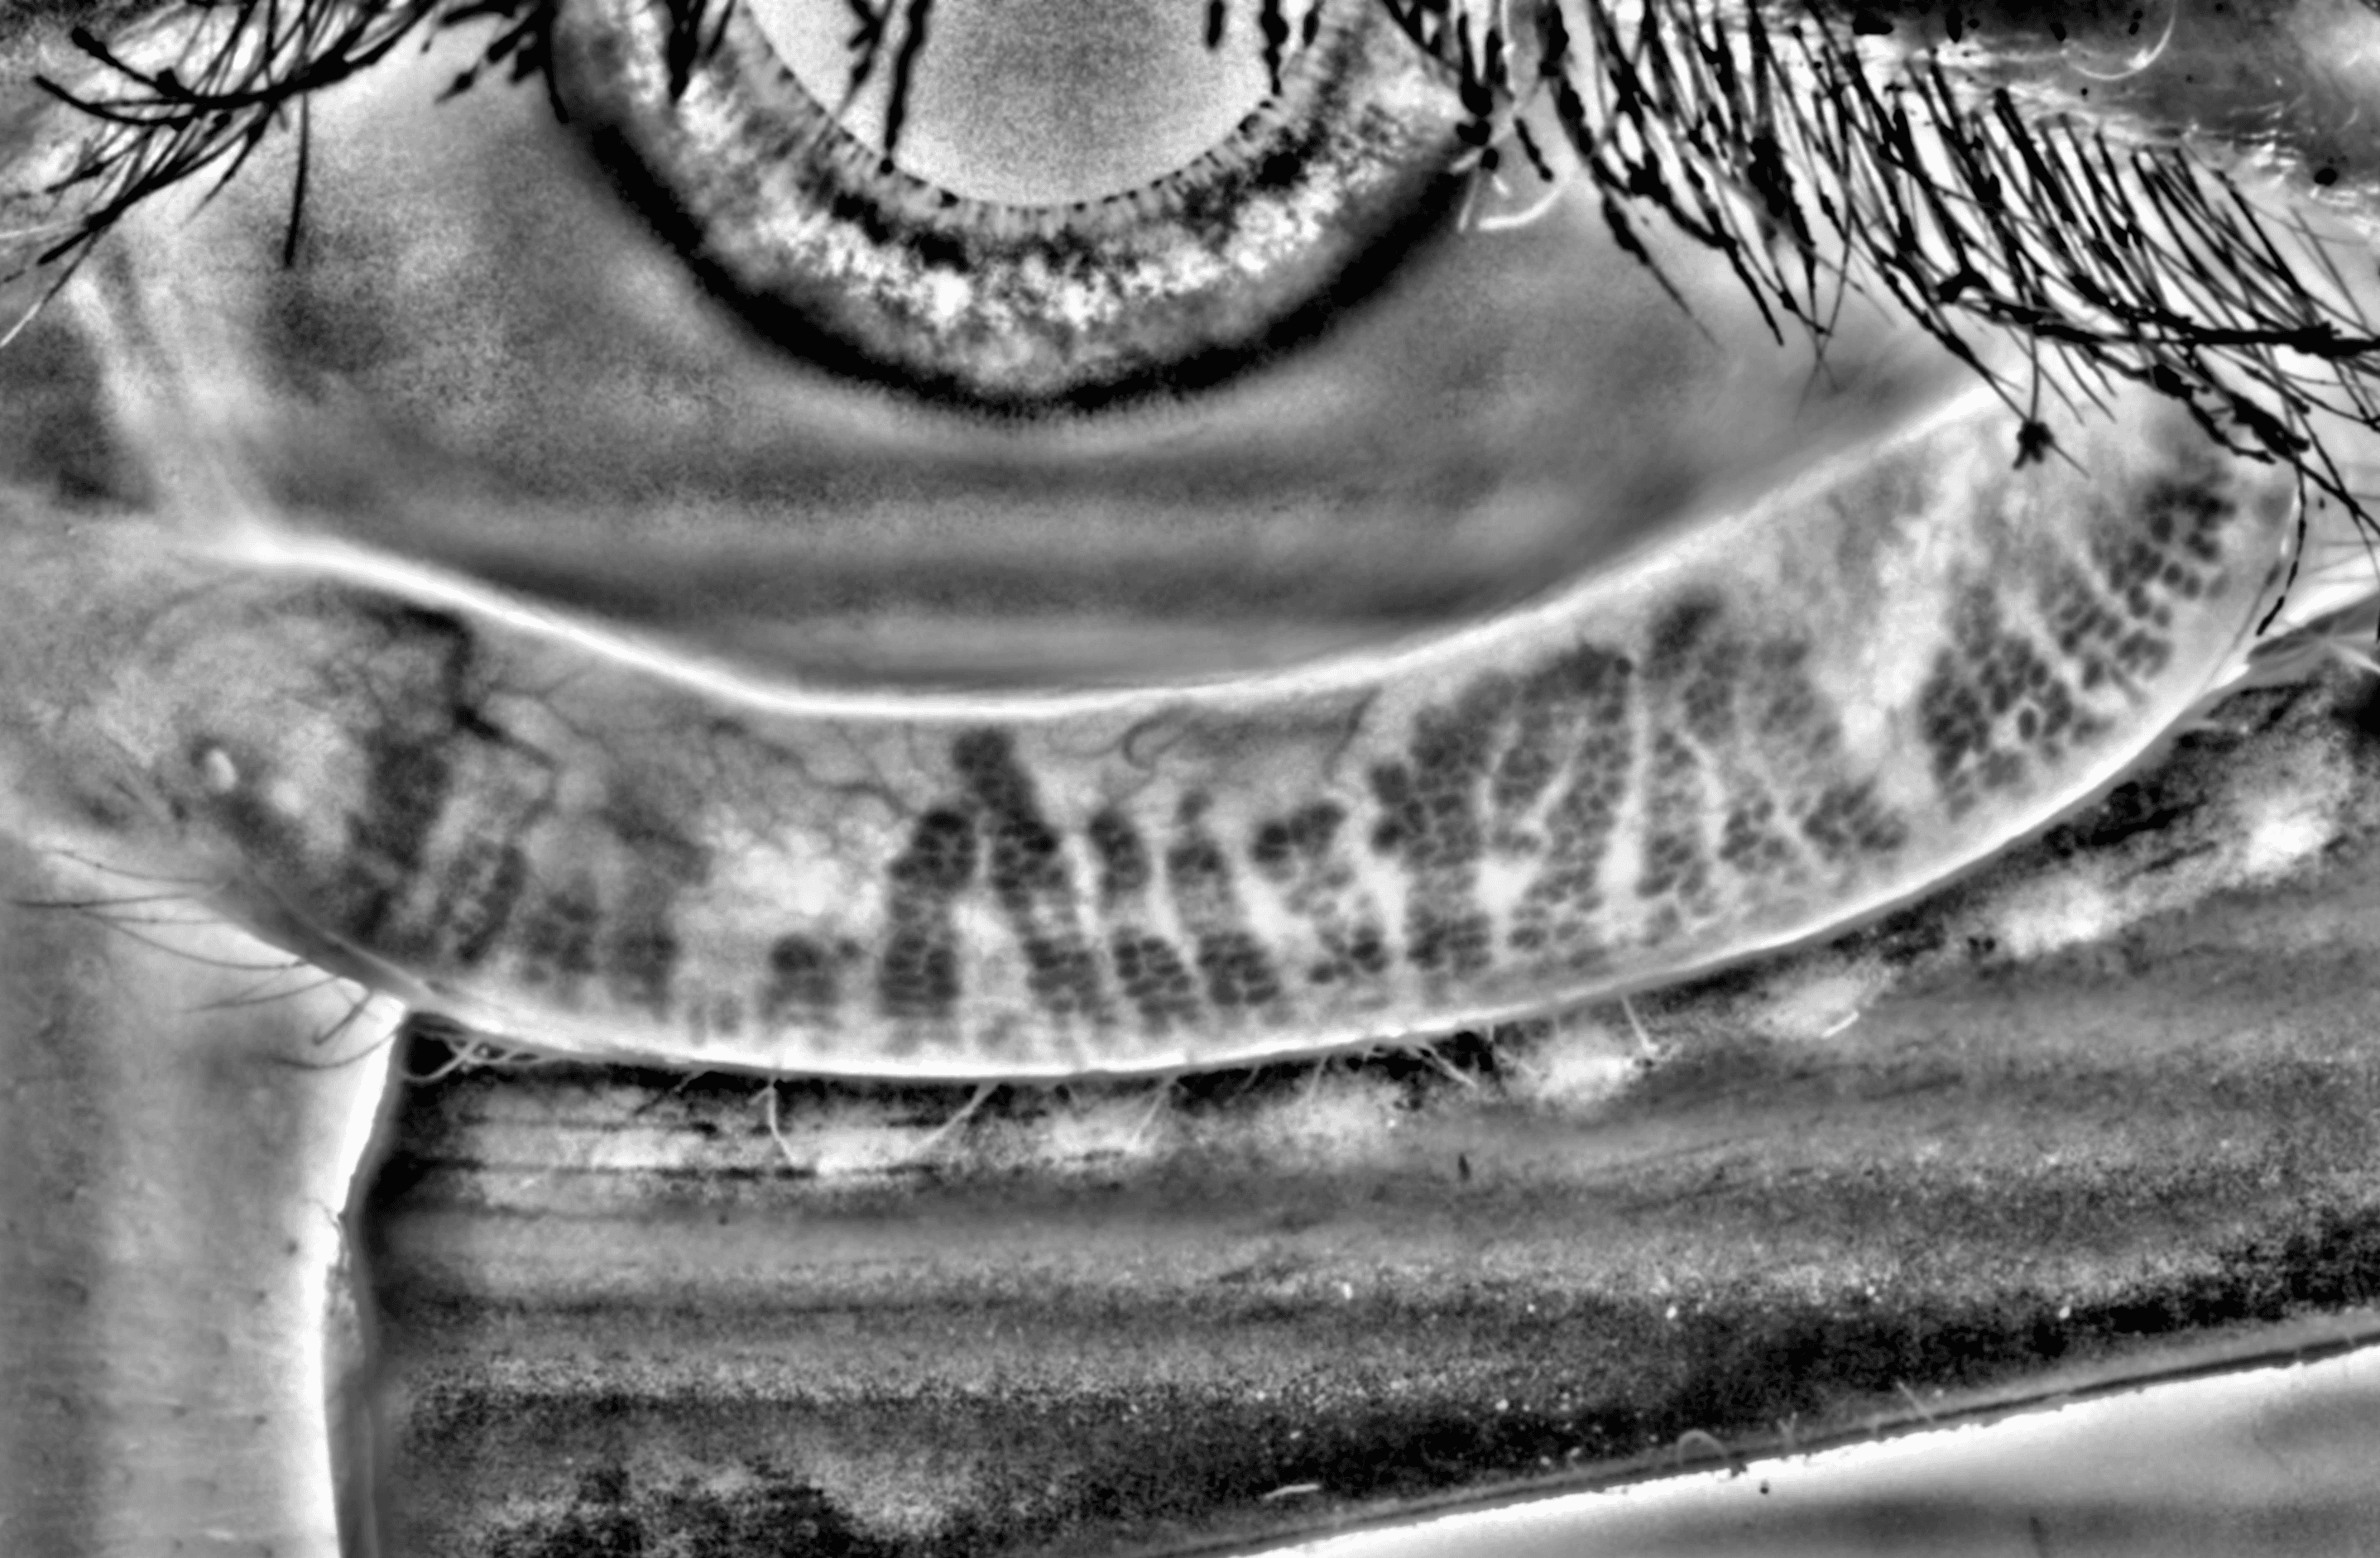

Capture and visualize meibomian gland structure, blink dynamics, tear film appearance, fluorescein imaging, and patient-reported symptoms using a single, compact device designed to integrate seamlessly into existing clinical setups.

See More with AI-Assisted

Real-Time Visualization

AI-assisted image processing enhances the visibility of ocular surface features, reducing time required manual image adjustments and allowing clinicians to focus on efficient clinical review. Operating directly on the live video stream, it provides immediate visual feedback that supports faster alignment, more confident image capture, and a smoother workflow.